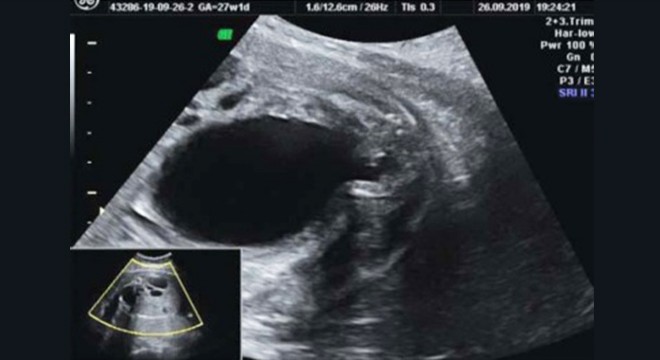

Bu kanalda deformasyon oluşmasına sebep olan dokuya da “valv” adı verilir. Anne karnında alt idrar yollarına bağlı olarak oluşan PUV, söz konusu valv dokusu nedeniyle idrar atılımını engeller. Dolayısıyla mesaneden dışarıya doğru atılamayan idrar, bu alanda sıkışır. Daha ilerleyen yaşlarda PUV hastalığının ortaya çıkması ise hidronefroz adı verilen başka bir sağlık sorununa neden olabilir. Hidronefroz temel olarak idrar kanallarının tamamen idrarla dolup şişmesi anlamına gelir.

Posterior Üretral Valv tedavisi, özellikle son dönemde tıp bilimi alanında yaşanan gelişmelerle birlikte önemli ölçüde sonuç veren bir uygulamadır. PUV hastalığı, hamileliğin ilk dönemlerinde bebeğin hayati fonksiyonlarını etkileyebilecek niteliktedir. Dolayısıyla hastalığın tespit edilmesi ve tanının konulmasının ardından tedavi sürecine başlanmalıdır. Tedavi süreci, büyük oranda endoskopik yaklaşımlarla gerçekleştirilir. Fetüsün idrar torbası bölümüne endoskopik uygulamalarla kamer yardımıyla girilir.

Kamera ile bölgede yaşanan sorunun ortaya çıkardığı deformasyon ve soruna neden olan oluşumlar tespit edilir. Prof. Dr. Selahattin Kumru tarafından da gerçekleştirilen Posterior Üretral Valv tedavisi sürecinde en önemli nokta bebeğin hayatta kalmasını sağlayarak, böbreğin fonksiyonlarını tam anlamıyla yerine getirdiğinden emin olmaktır. Tedavi aşamasında üretral valv, lazer yöntemiyle açılır ve tıkanıklık giderilir. Bu işlemin gerçekleştirilmesiyle birlikte mesanede idrara birikimi sorunları ve bebeğin idrarı dışarı atamaması gibi olumsuzluklar ortadan kalkar ve böbrekler işlevini yerine getirir.